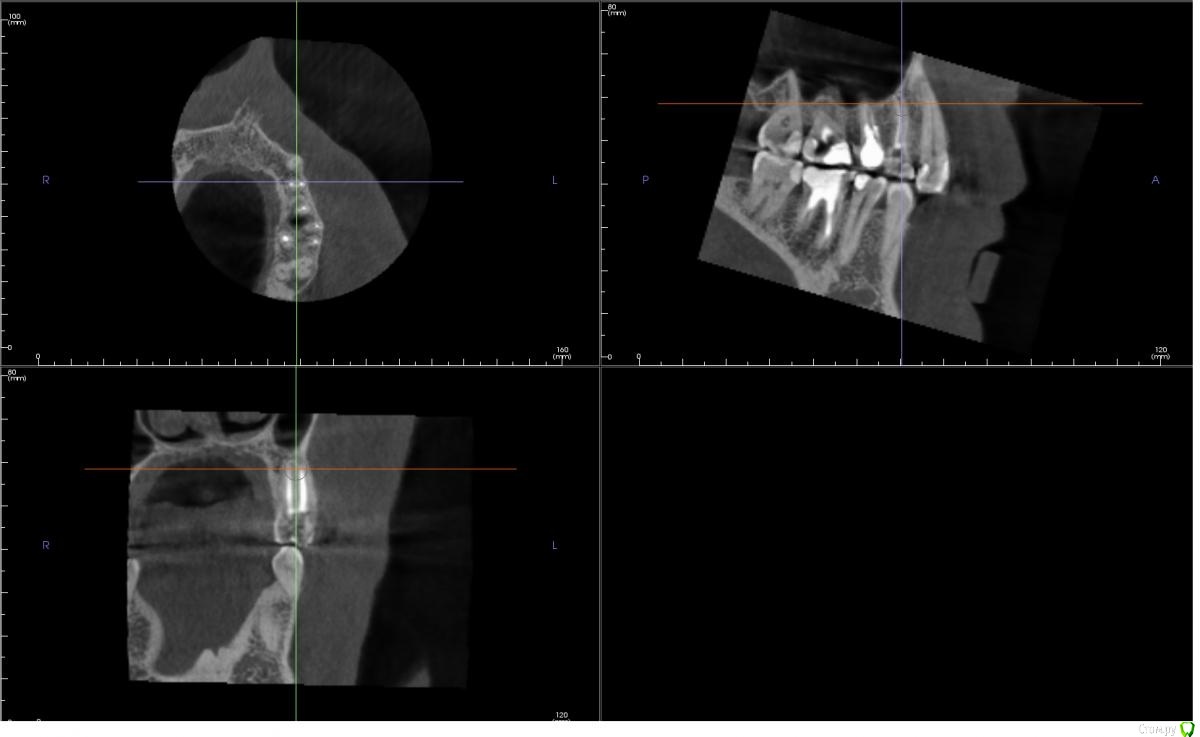

andreymir Опубликовано 7 марта, 2021 Поделиться Опубликовано 7 марта, 2021 Было проведено лечение каналов из-за кисты на 24 зубе. 2 канала, 2 корня. На КТ каналы запломбированы, но между каналами на всем протяжении каналов прослеживается затемнение. В описании, ранее сделанного КТ (в процессе лечения) рентгенологом указано, что корни срослись (каналы?) на всем протяжении. Затемнение между каналами на всем протяжении зуба на ранее сделанном КТ, к которому было приложено данное описание, не прослеживается. Это затемнение обнаруживается только на КТ, выполненном сразу после лечения. Затемнение между каналами на последнем КТ выходит за границу зуба, за границу кости и сливается с синусом. Скрины с КТ прилагаю к данному сообщению.Вопросы:1. Что это за затемнение? Не мог же появится новый канал в процессе лечения? Или это не заполненная пломбировочным материалом часть канала? Или это полость, которая соединяет каналы на всем протяжении?2. Верно ли, что раз затемнение выходит за границу зуба, то это означает, что стоматолог "перестарался", проткнул кость и провалился в синус? И теперь через весь зуб проходит не заполненный пломбировочным материалом канал связанный с синусом?3. Что делать с таким зубом? Можно ли ставить коронку, его нужно перелечить или он безнадежен и его пора менять на имплант?Спасибо!КТ ниже выполнено сразу после ЗАВЕРШЕНИЯ леченияКТ ниже выполнено в ПРОЦЕССЕ леченияЕсть КТ до начала лечения, если необходимо могу приложить в следующем сообщенииХорошего дня! Ссылка на комментарий

andreymir Опубликовано 7 марта, 2021 Автор Поделиться Опубликовано 7 марта, 2021 (изменено) у вас все нормально, не ищите проблем там где их нет. Зуб восстанавливайте искусственной коронкойБольшое спасибо вам за ответ, но я был бы вдвойне признателен за более обстоятельный ответ. Меня слегка тревожит первое изображение. Можете уточнить, что за затемнение проходит через весь зуб между двумя каналами на первом изображении и выходит в синус? Спасибо! Изменено 7 марта, 2021 пользователем andreymir Ссылка на комментарий